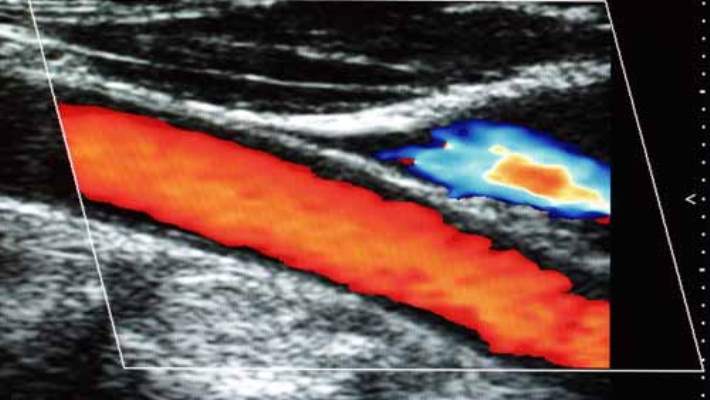

Doppler Ultrasonu

Doppler ultrasonu, gönderilen yüksek frekanslı ses dalgalarının (ultrason) kırmızı kan hücrelerinize çarpıp geri gelmesiyle kan akışınızı ve kan basıncınızı ölçmekte kullanılan invaziv olmayan bir testtir. Sıradan bir ultrason görüntüler oluşturmak için ses dalgaları kullanır ancak kan akımını göstermez.

Doppler ultrasonu, yoğunluğundaki (sıklık) değişim oranını hesaplayarak kanın ne kadar hızlı aktığını değerlendirebilir. Doppler ultrasonu sırasında, ultrason görüntüleme konusunda eğitimli bir teknisyen (sonograf), vücudunuzun incelenen bölgesi üzerindeki deriye elle taşınabilen ve bir kalıp sabun büyüklüğündeki bir düzeneği (transdüser) gerektiği şekilde bir bölgeden diğerine gezdirecek biçimde bastırır. Test, röntgen görüntülerinde ortaya çıkması için damarlara boya enjekte edilmesini içeren arteriyografi ve venografi gibi daha invaziv işlemlere bir alternatif olarak kullanılabilir.